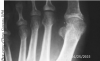

Study Compares First MPJ Arthrodesis In Patients With OA And RA

First metatarsophalangeal joint (MPJ) arthrodesis can be beneficial for patients with osteoarthritis and rheumatoid arthritis. However, a recent study in the

Journal of Foot and Ankle Surgery investigates whether each patient population heals differently.

The study authors analyzed 155 first MPJ fusions, 116 for patients with osteoarthritis pain and 39 for patients with rheumatoid arthritis. Patients with rheumatoid arthritis experienced a statistically shorter time to fusion while the incidence of fusion was 94 percent for patients with rheumatoid arthritis and 89 percent for those with osteoarthritis, according to the study.

Lead author Christopher Hyer, DPM, FACFAS, is not sure why rheumatoid arthritis patients achieve fusion quicker than osteoarthritis patients. In his practice, he saw results similar to those of the study for several years. In theory, the disease process with osteoarthritis, which has sclerotic, hyperdense bone, is more difficult biologically to heal, according to Dr. Hyer, the Fellowship Director and an attending physician at the Orthopedic Foot and Ankle Center in Westerville, Ohio.

Are there specific challenges for surgeons when performing first MPJ arthrodesis in arthritic patients? For rheumatoid arthritis patients, Dr. Hyer says one should confirm that the patients are off any disease modifying anti-rheumatic drugs (DMARDs) or prednisone if at all possible as both inhibit bone healing. For osteoarthritis patients, he suggests being hypervigilant in joint prep with thorough removal of dense subchondral bone and exposure of raw cancellous bone on both sides of the joint.